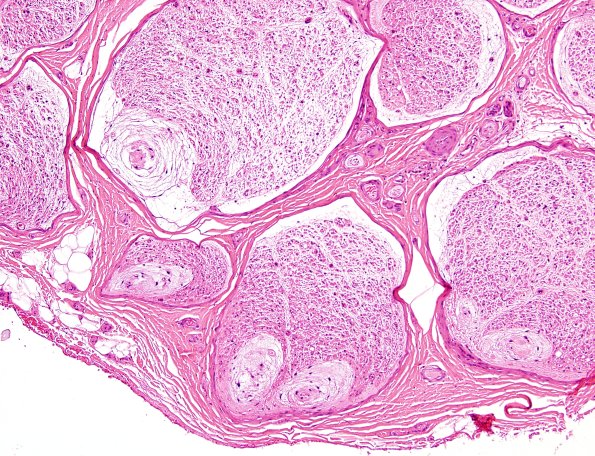

11A2 Renaut body (Case 11) H&E 4

A sural nerve rich in RB. (H&E)